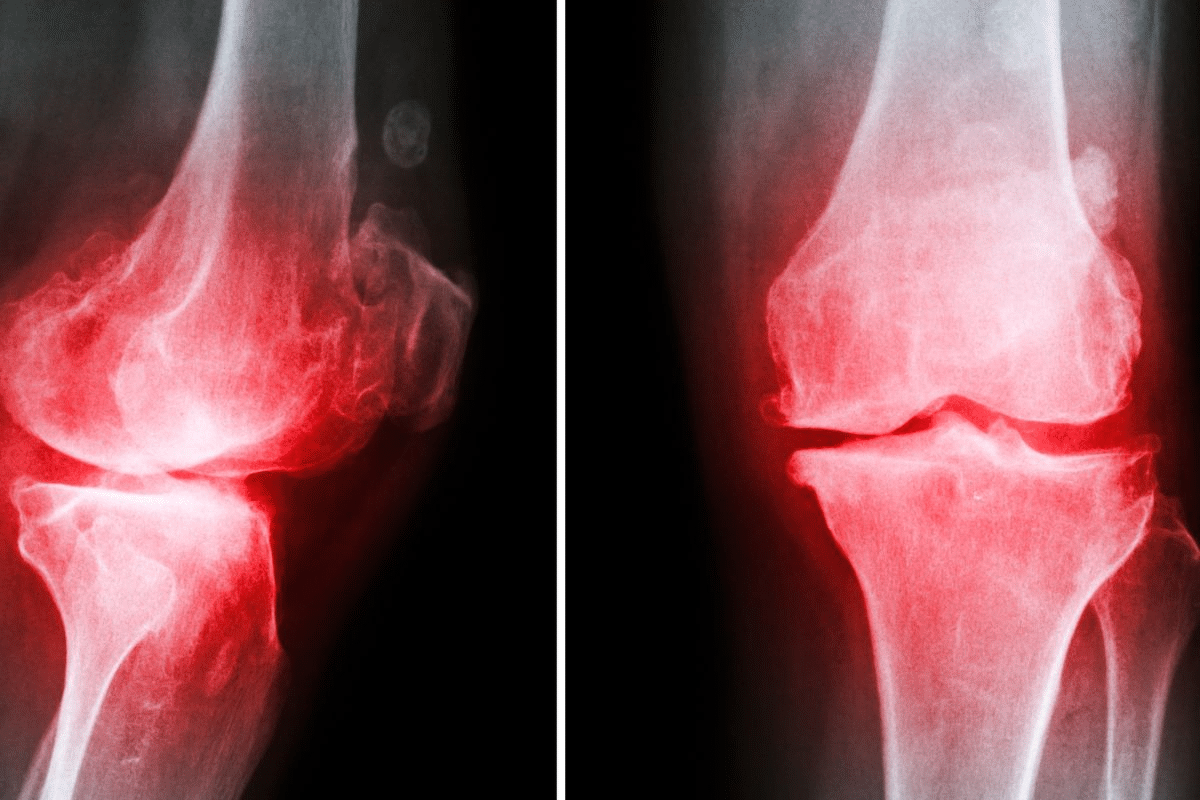

Osteoarthritis happens when cartilage in joints breaks down. This leads to bones rubbing against each other, causing a lot of discomfort. It can affect any joint, but often hits the hands, knees, hips, and spine. The degeneration of cartilage makes joints less mobile and painful.

Cartilage breakdown is a key sign of osteoarthritis. When cartilage wears down, joints can’t absorb shock or move smoothly. This can cause bone-on-bone contact, leading to pain and inflammation.

Bone spurs, or osteophytes, can also cause flare-ups. These are bony growths that form to repair damage. But they can sometimes irritate tissues, making symptoms worse.